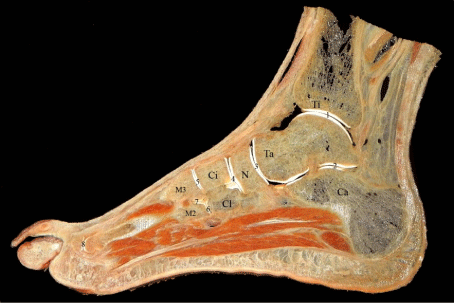

Figure 1: A 2 mm sagittal section of the foot through second and third toes.

Anatomical details are clearly visible. Only bones and articulations were

marked to avoid confusion. Ti: Tibia, Ta: Talus, Ca: Calcaneus, N: Navicular

bone, Ci: Intermediate cuneiform bone, Cl: Lateral cuneiform bone, M2: Base

of second metatarsal bone, M3: Base of third metatarsal bone, 1: Talocrural

joint, 2: Subtalar joint, 3: Talonavicular joint, 4: Cuneonavicular joint, 5-6:

Tarsometatarsal joints, 7: Intermetatarsal joint and 8: Metatarsophalangeal

joint.